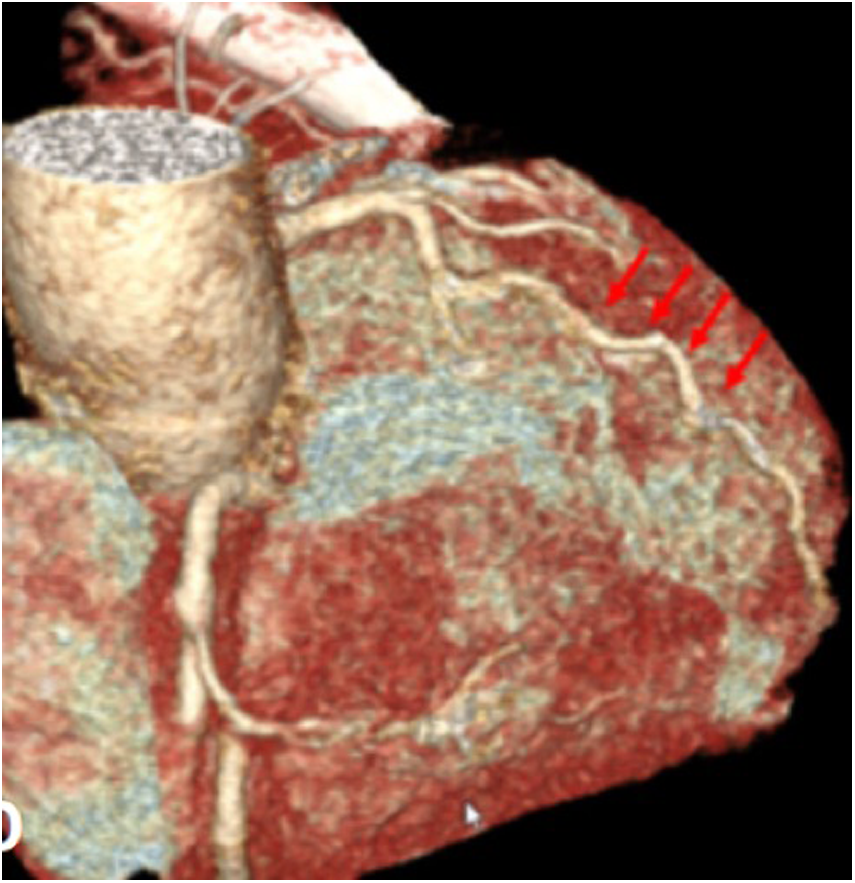

The pre-discharge echocardiography showed normal biventricular function without valvular lesion or intracardiac shunts. Cardiac CT-scan showed patent coronary arteries (Figure 5).